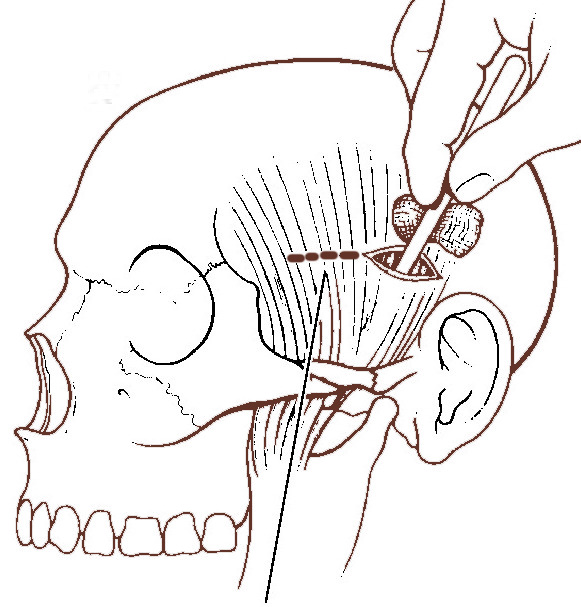

Gillie's technique of reducing fracture zygoma:

Small incision is made over temporal area superficial temporal artery is avoided

Auricularis superior muscle is cut along the line of its muscle fibers

Temporalis fascia is cut with a knife

Periosteal elevator is inserted through the incision and the fractured fragment is elevated. A gauze piece is used as a leverage

Figure showing fracture arch of zygoma being reduced.